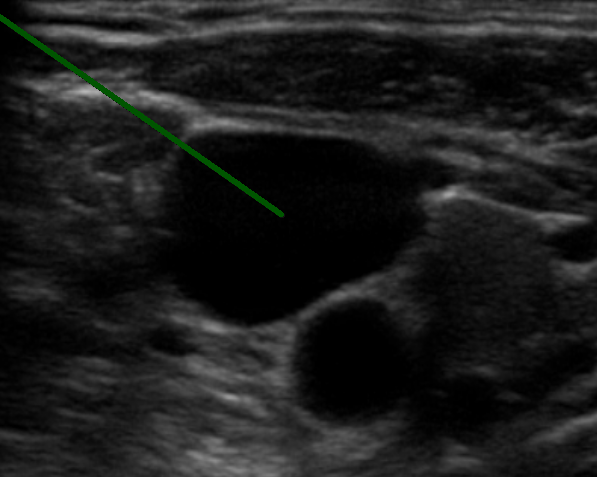

먼저 초음파를 통해 오른쪽 내경정맥을 확인합니다.

다음은 초음파를 보고 우측 내경정맥을 바늘로 천자합니다. 바늘의 굵기는 0.8mm 짜리를 씁니다.